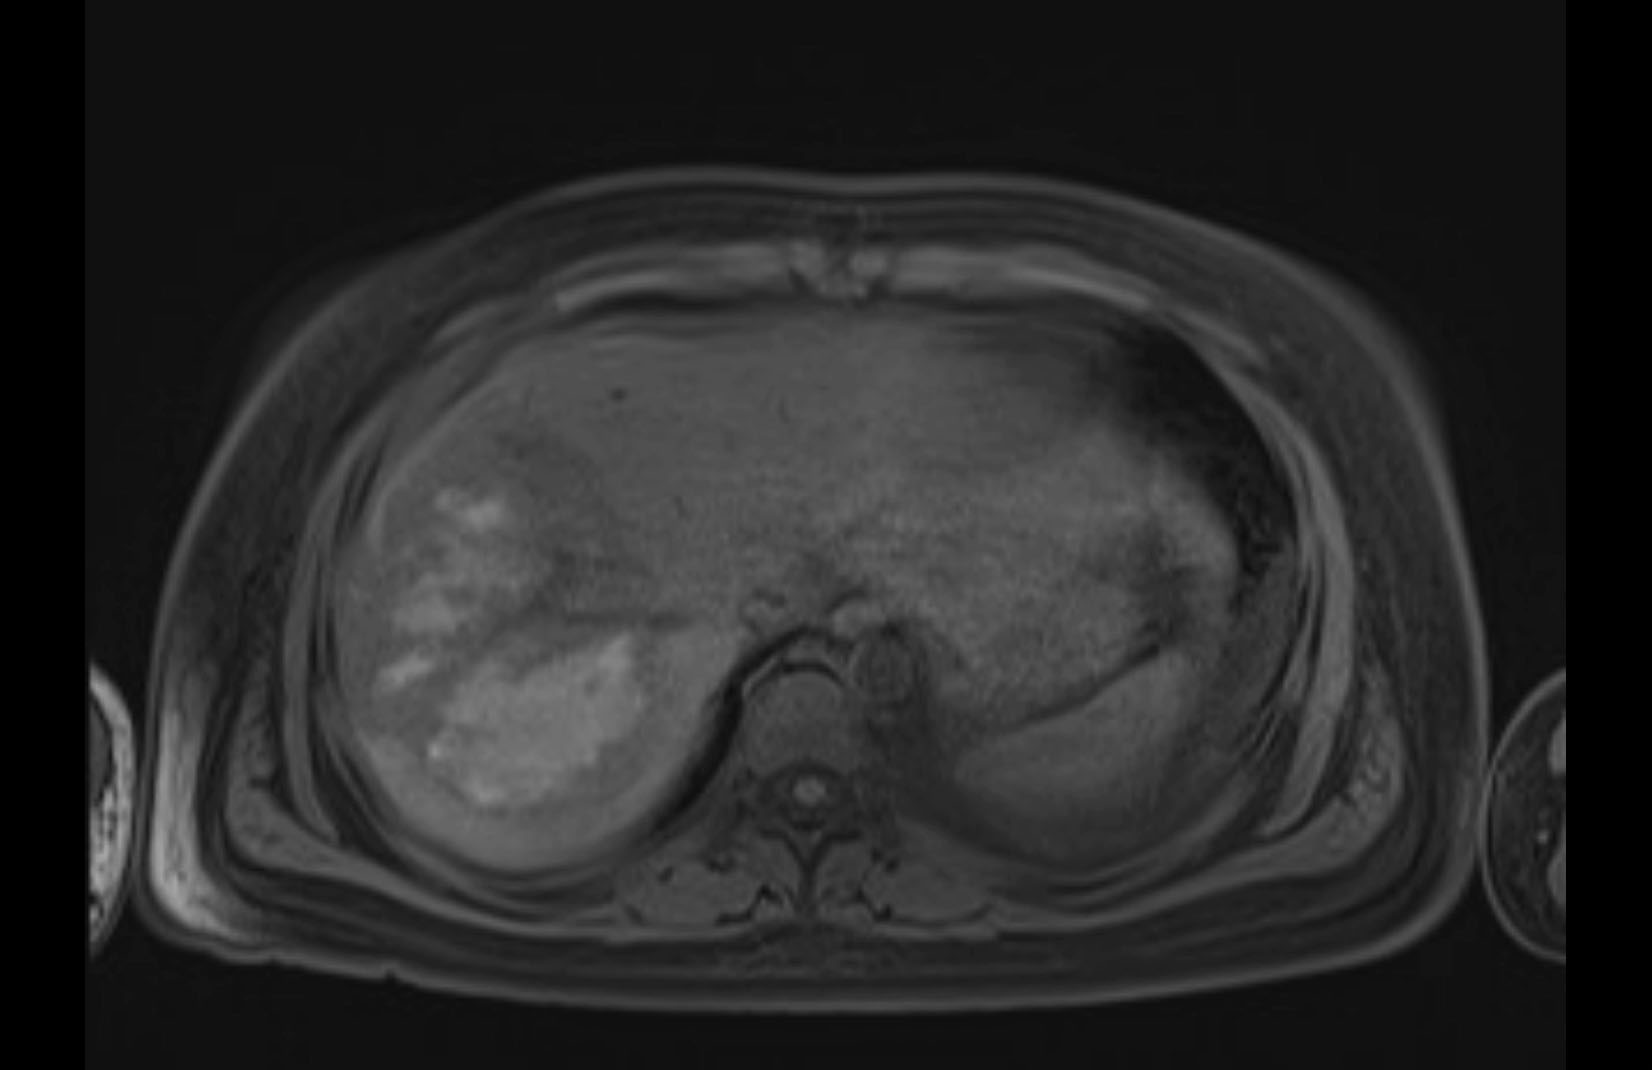

MRI T1

MRI T2